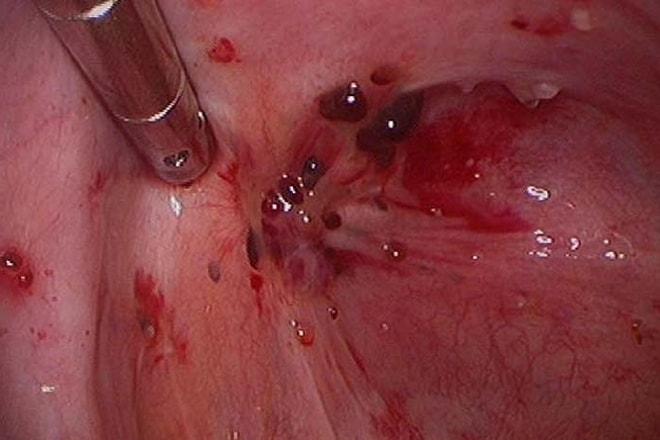

Гистологическое строение также играет важную роль в клинической картине и влияет на прогноз заболевания. Биопсия выполняется с использованием лапароскопического оборудования. Патоморфологи выделяют несколько форм эндометриоза яичников на основе проведенных анализов:

- железисто-кистозная форма (характеризуется выраженным стромальным и железистым компонентом);

- кистозная форма, для которой характерны обычные, слабо кровоснабжаемые кисты.

Современные ультразвуковые методы наиболее точно показывают наличие кист. Важно оценить их размеры, количество и глубину расположения. В зависимости от фазы менструального цикла размеры образований могут значительно варьироваться. При проведении томографии картина поражения становится более ясной. Тем не менее, самым информативным методом остается лапароскопия. Это миниинвазивная, но все же хирургическая процедура. Решение о том, какие диагностические процедуры проводить, принимает сама женщина после получения полной информации о преимуществах и недостатках каждого метода.

Хирургическое вмешательство при эндометриозе проводится с помощью лапароскопии. Кисты диаметром более 30 мм не могут уменьшиться или исчезнуть без операции. В качестве подготовки может быть назначен курс консервативной терапии.